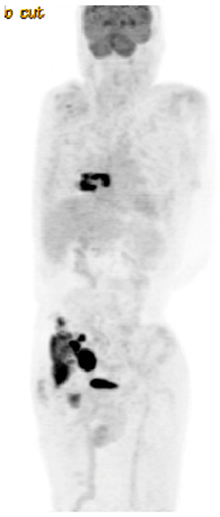

PET/CT: paravertebral soft tissue mass at T7 with extension into right lower lobe, right pelvic sidewall mass (maximum 6 cm)

CR on post-treatment PET/CT

14 months later, developed recurrent abdominal pain, PET/CT and biopsy confirmed recurrent DLBCL

CR on PET/CT at 3 months

Progression on PET/CT at 6 months post CAR-T-cell therapy